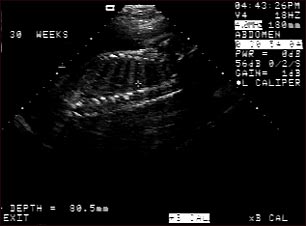

Ultrasonido de un feto normal; columna y costillas

Ultrasonido normal a las 30 semanas de gestación. En el centro de la pantalla se observa el perfil nítido de la columna vertebral y las costillas. La cruz se encuentra ubicada entre dos costillas justo por debajo de la columna vertebral.